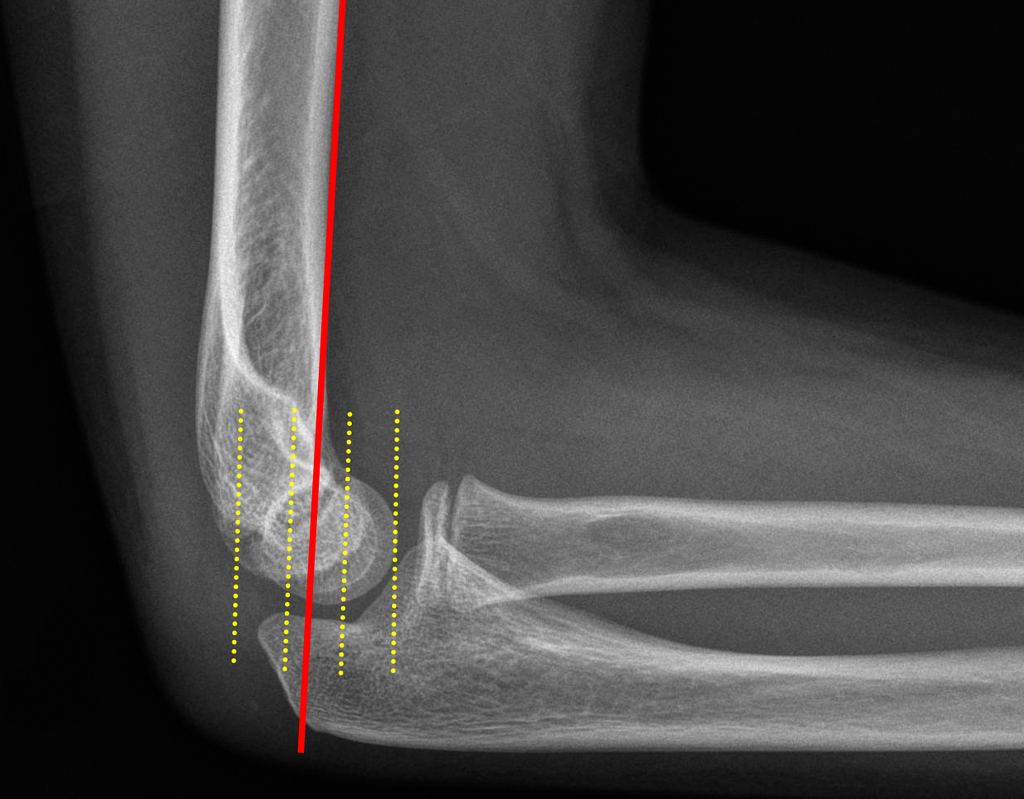

Radiocapitellar Line: line through the radial neck bisects the capitellum

radiocapitellar-line

Anterior Humeral Line: a line drawn along the anterior margin of the humerus should run through the middle third of the capitellum.

Baumann’s angle (carrying angle): Normal is 70 to 75 degrees.  A difference between extremities of just 5 degrees or more is abnormal.

Baumann's Angle

If you don’t see the obvious fracture, you can be “saved” by the sail sign and/or a posterior fat pad.  Also, make sure to look for the anterior humeral line – on the lateral view, a line drawn down the anterior humerus – if it intersects with the middle third of the capitellum, that is normal – it not, suspect a supracondylar fracture.

The radiocapetellar line runs along the radial neck through the radial head and should line up nicely with the capitellum. If not, assume a fracture-dislocation.